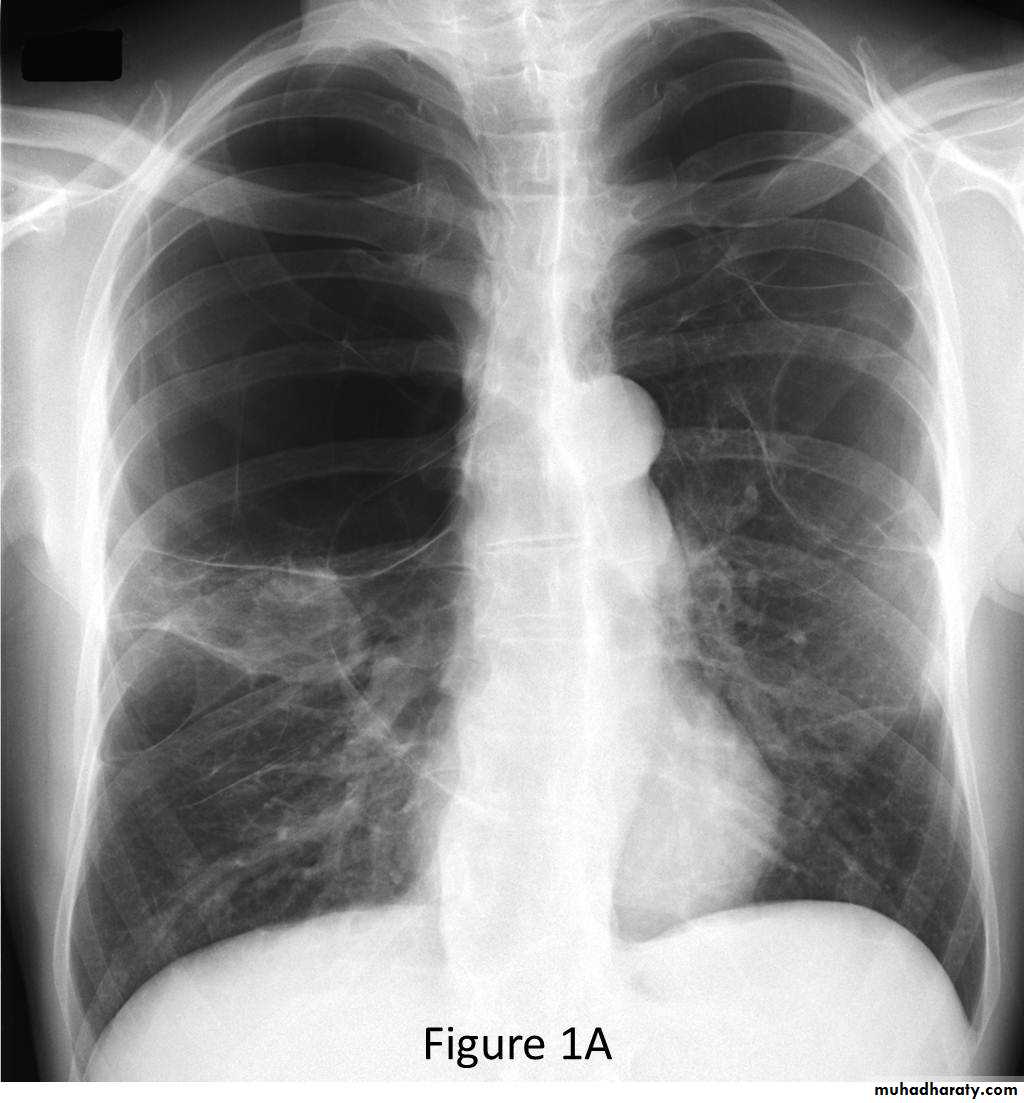

CXR:

• CXR: lung surrounded by thick irregular pleura with multiple nodules with extension to nearby structures.